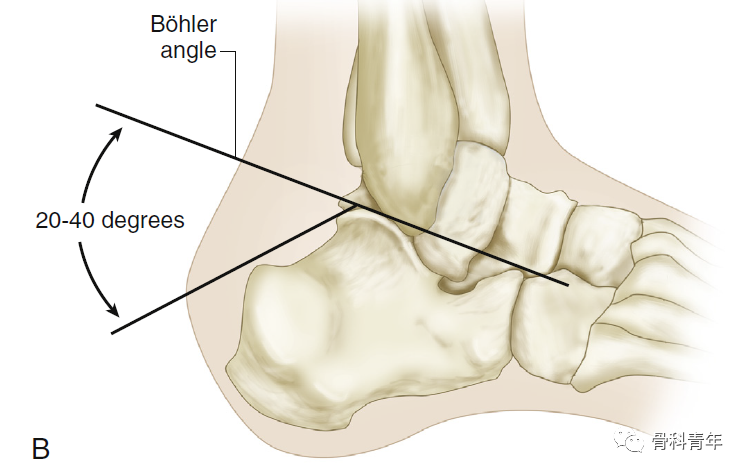

跟骨骨折骨性解剖包括Gissane角Böhler角。在入路中主要注意腓骨长短肌腱、胫后血管及腓肠神经。

Böhler角:即跟骨结节关节面角。跟骨结节与跟骨后关节突连线,与跟骨前后关节突连线夹角,正常为35-45°。后关节面塌陷时该角减小。